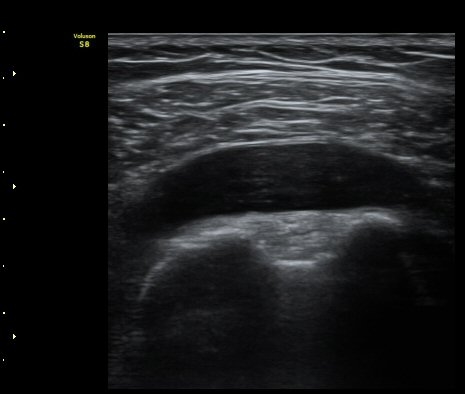

°Ë»ç¿¡¼­ Ç÷·ùÁõ°¡´Â °üÂûµÇÁö ¾Ê´Â´Ù(±×¸² 1, 2).   À̵ιڱ٠¾Æ·¡ Ⱦ´Ü¸é°Ë»ç¿¡¼­

°üÀý³» ¼ö¾×Àú·ù´Â ¶Ñ·ÈÇÏÁö ¾Ê´Ù(±×¸² 3). ±Ø»ó°Ç Á¾´Ü¸é°Ë»ç¿¡¼­ Á¡¾×³¶³» ¼ö¾×